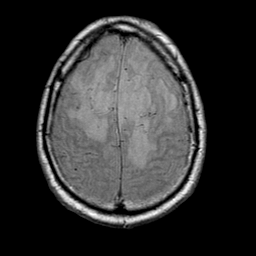

Meningioma, MR Study #1 -- Slice #16

[Home][Help][Clinical] Slice 16